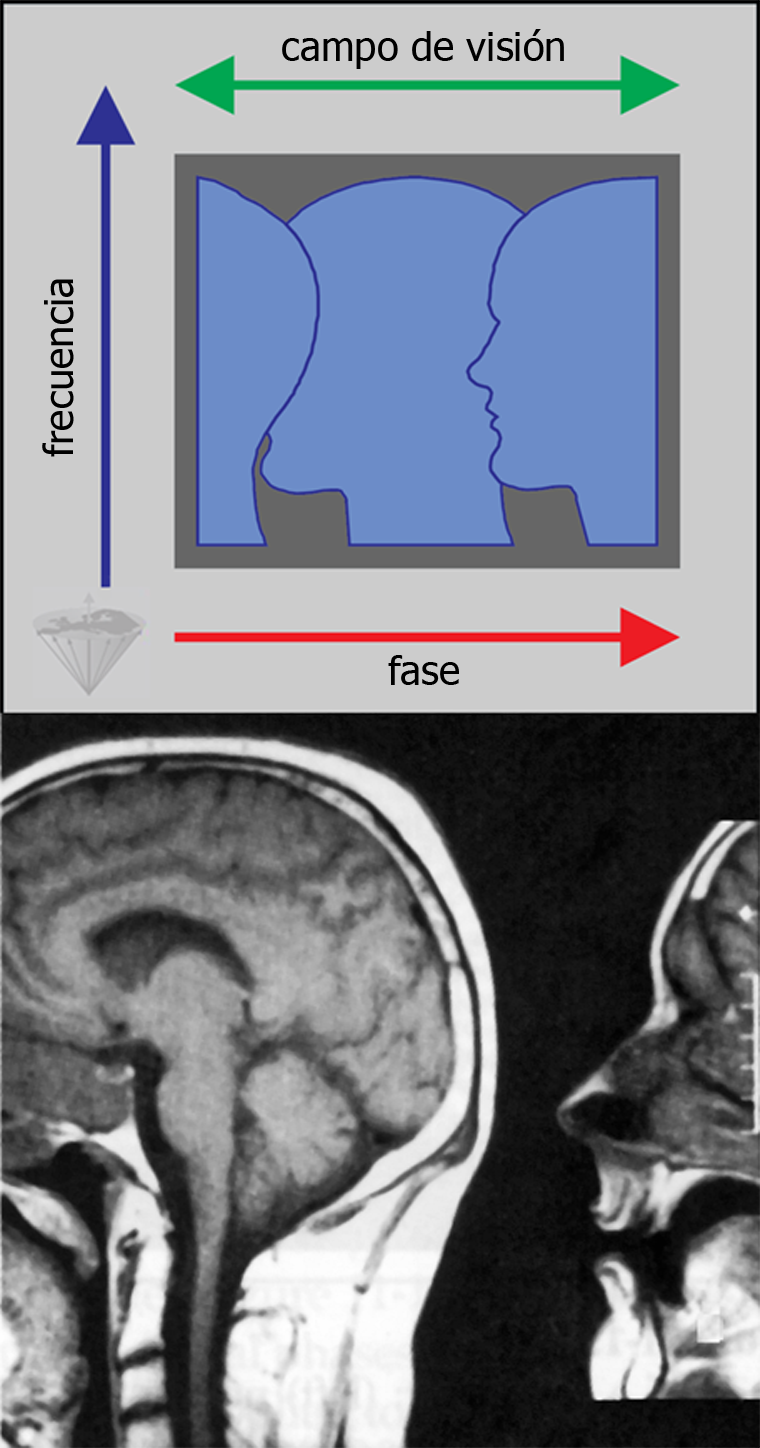

Figura 17-15:

Backfolding artifact resulting from the sample being larger than the field of view in the phase en­­cod­­ing di­rec­tion, which is orientated left-right in this example.